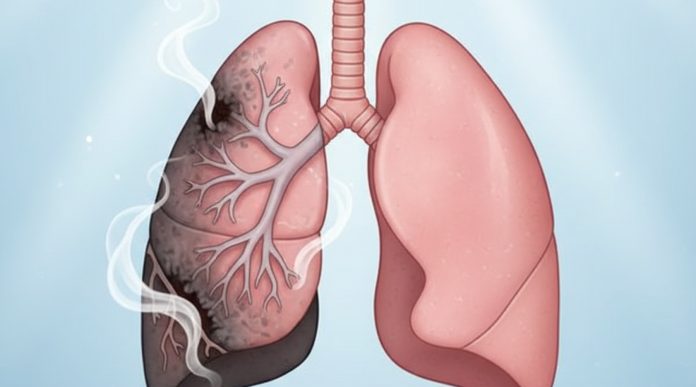

Pušenje je jedna od najštetnijih navika za pluća, ali dobra vijest je da se naše tijelo posjeduje izvanrednu sposobnost oporavka. Ipak, proces nije trenutan – ovisi o duljini pušenja, dobi, općem zdravlju i eventualnim postojećim oštećenjima dišnog sustava.

Dugoročni oporavak pluća traje najduže. Nakon 5 godina, rizik od raka pluća počinje se smanjivati, iako ne pada na razinu nepušača. Tek nakon 10 do 15 godina rizik postaje upola manji nego kod aktivnog pušača. No, važno je naglasiti: iako se pluća mogu značajno oporaviti, neka oštećenja – osobito kod onih koji su pušili desetljećima – mogu biti trajna.